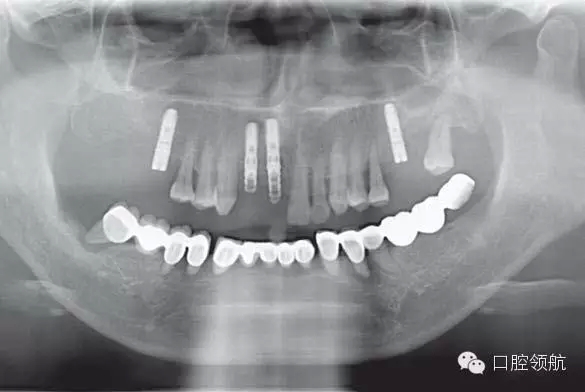

圖6-8 下頜術前全景片

下頜為十數年前制作的三組金屬烤瓷橋修復體。右下4、5、7帶缺失的6;右下3、1及左下1、2帶缺失的右下2;左下3、4、5、8帶缺失的6、7,左下8修復后牙齒自然脫落,全景片無左下8的影像。幾乎所有的余留牙周圍的骨質均吸收到根尖1/3。臨床上三組下頜金屬烤瓷橋均有較大幅度的松動(圖6-7,圖6-8)。